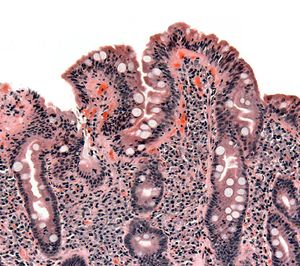

خزعة من الأمعاء الدقيقة تبين الداء البطني ظاهراً بتقصف الخملات، crypt hyperplasia, والخلايات الليمفية تتغلغل في crypts | |